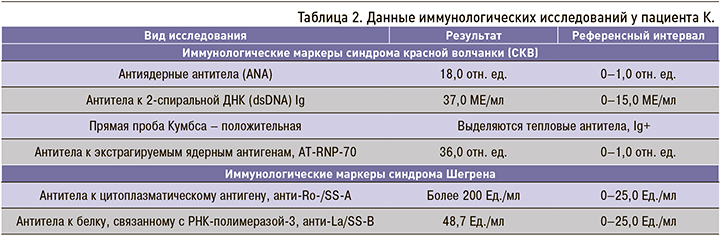

Результаты иммунологических исследований приведены в таблице 2.

Результаты иммунологических исследований приведены в таблице 2.

На основании клинической картины, иммунологических и биохимических результатов обследования установлен следующий диагноз: М 32.1. Системная красная волчанка, хроническое течение, активность высокая (SELENA/SLEDAI 8 баллов), с поражением кожи (эритема), суставов (артралгии, кисть Жакку), мышц (миалгии), легких (адгезивный плеврит, фиброзирующий альвеолит), гематологическими нарушениями (анемия, Кумбс-позитивная, лейкопения, тромбоцитопения), иммунологическими нарушениями (а-нДНК+, АНФ+). Синдром Шегрена; паренхиматозный сиалоаденит, иммунологические нарушения (анти-Ro/SS-A, анти-La/SS-B, РФ+, АНФ+).